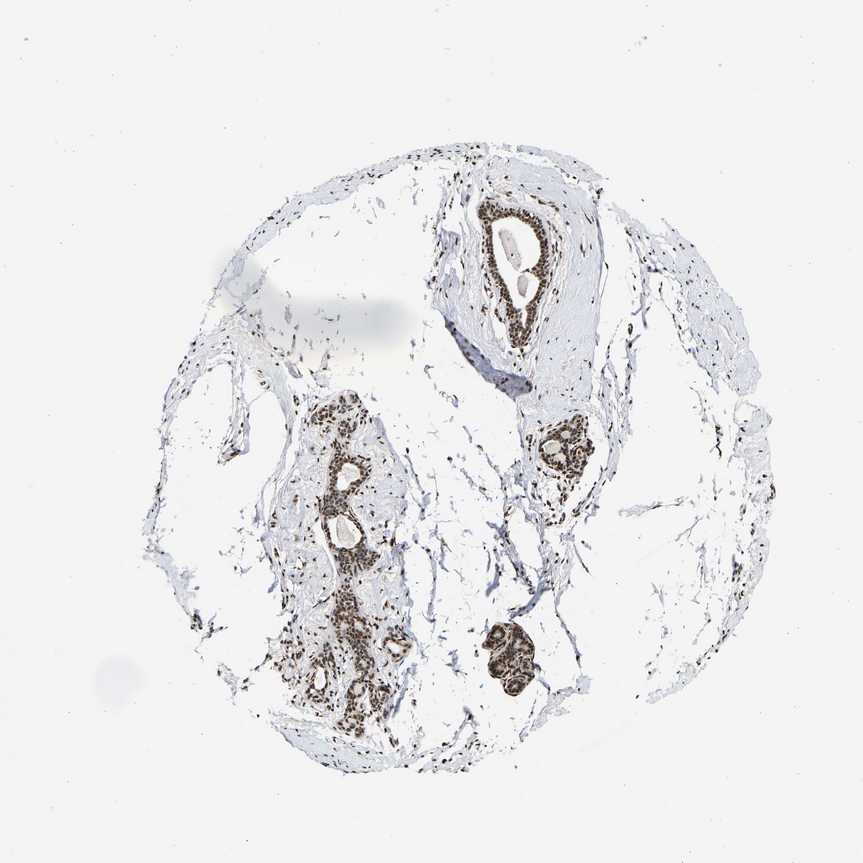

BREAST - Antibody stainingi

Antibody staining in the annotated cell types in the current human tissue is reported as not detected, low, medium, or high, based on conventional immunohistochemistry profiling in selected tissues. This score is based on the combination of the staining intensity and fraction of stained cells.

Each image is clickable and will lead to virtual microscopy that enables deeper exploration of all samples and also displays staining intensity scores, fraction scores and subcellular localization as well as patient and tissue information for each sample.

Antibody HPA019697Antibody CAB013718

Adipocytes HighNot detected

Glandular cells HighLow

Myoepithelial cells MediumLow